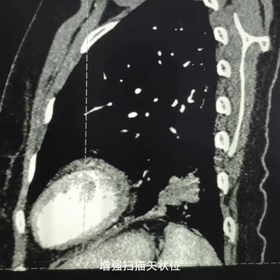

胸部CT平扫

矢状位增强扫描

轴位增强扫描